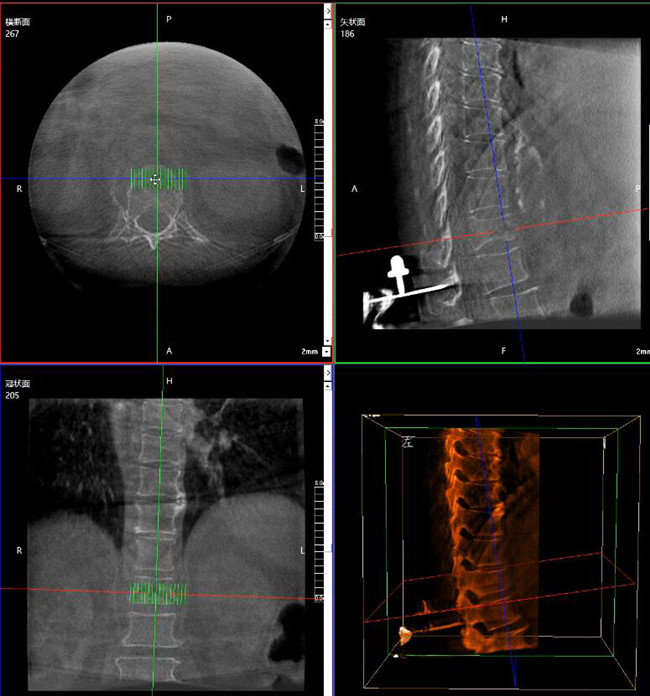

步驟一:C形臂三維重建+機(jī)器人手術(shù)規(guī)劃

使用普愛醫(yī)療三維C形臂對患者進(jìn)行胸椎影像掃描及三維重建,圖像被同步傳輸?shù)狡諓坩t(yī)療骨科機(jī)器人導(dǎo)航系統(tǒng)。

借助骨科機(jī)器人的規(guī)劃軟件進(jìn)行術(shù)前手術(shù)路徑模擬規(guī)劃,找到穿刺位置和角度,操作機(jī)械臂快速完成手術(shù)入點(diǎn)的準(zhǔn)確定位。

*術(shù)前規(guī)劃